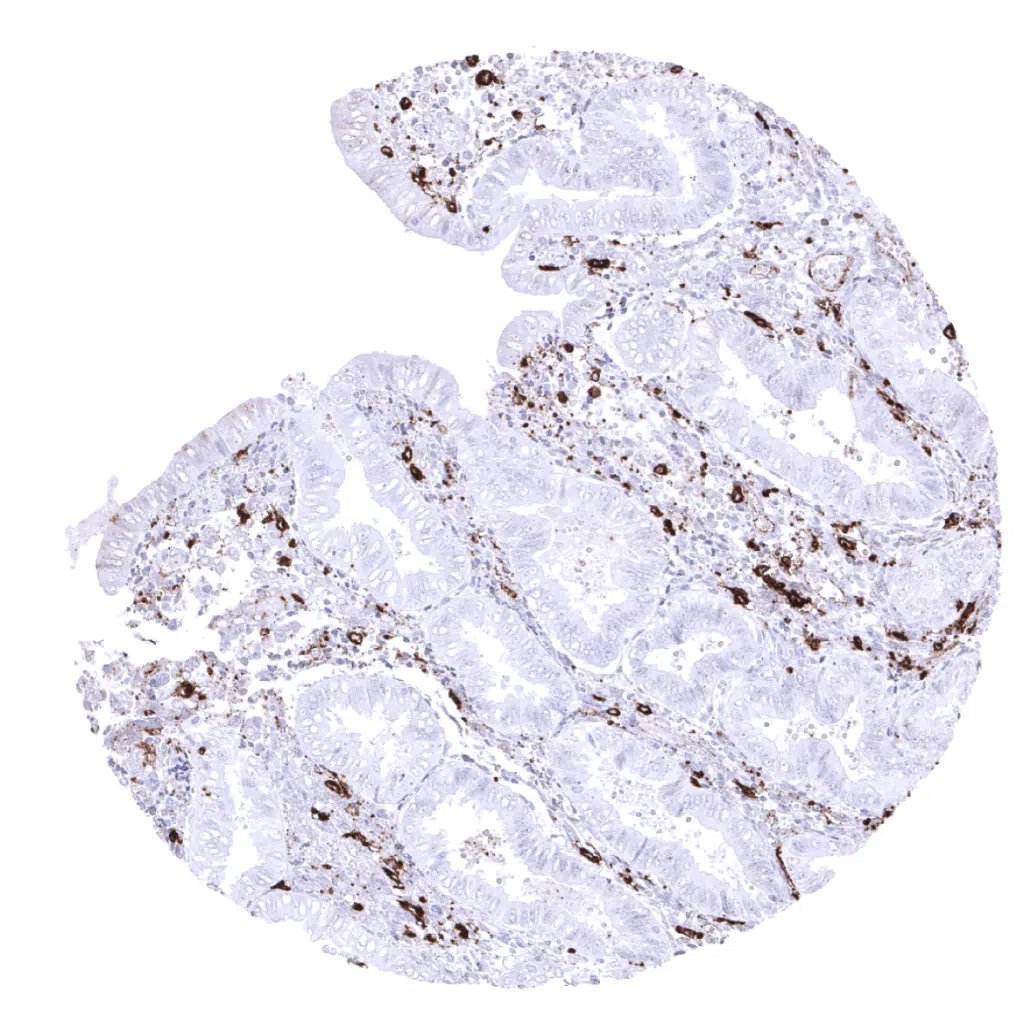

Ileum, mucosa: A membranous and cytoplasmic epithelial cell HLA-DRa staining of variable intensity is regularly seen in the ileum.

Duodenum, mucosa: The strongest membranous and cytoplasmic epithelial cell HLA-DRa staining occurs in the duodenum.

Stomach, antrum: A cytoplasmic and membranous HLA-DRa staining is often seen in the surface epithelium of the stomach.

Stomach, corpus: A cytoplasmic and membranous HLA-DRa staining is often seen in the surface epithelium of the stomach.